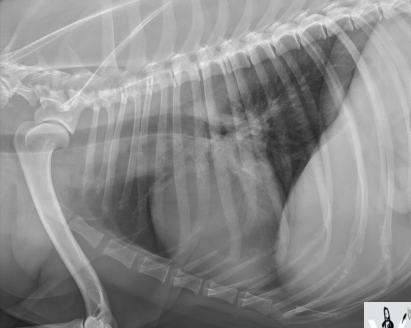

Quel est votre conclusion radiographique? Énumérez quelques diagnostics différentiels.

=> masse splénique

Ddx : néoplasme, granulome, kyste, hématome, nodule hyperplasique